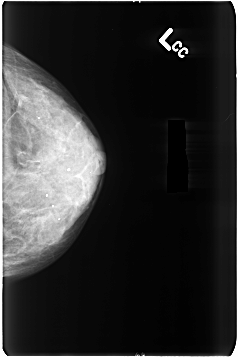

B_3496_1.LEFT_CC

LEFT_CC LINES 4640 PIXELS_PER_LINE 3088 BITS_PER_PIXEL 12 RESOLUTION 50 NON_OVERLAY